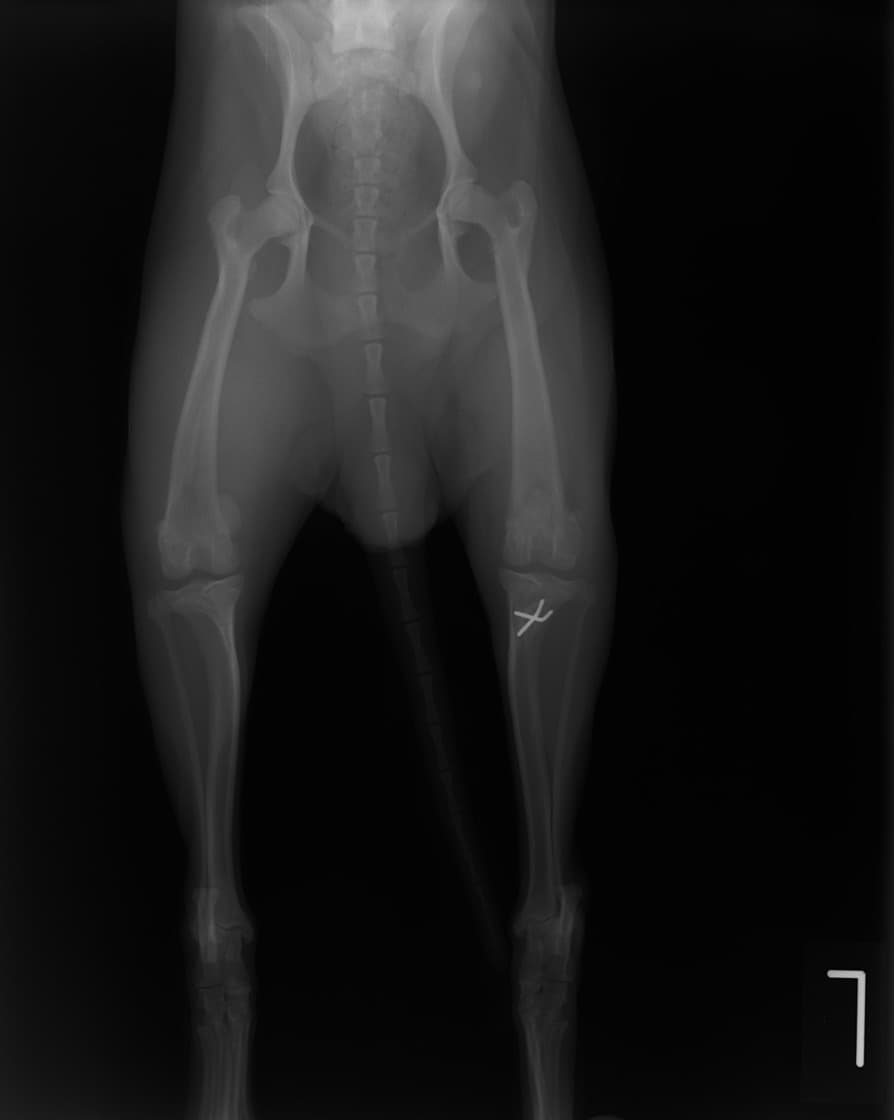

■ 症例22 ポメラニアン 1歳5か月 去勢雄

左後肢の挙上を主訴に来院した。整形学的検査、レントゲン検査より左右の膝蓋骨脱臼(左GradeⅡ〜Ⅲ、右Grade Ⅱ)を認めた。また、脛骨の前方引き出し試験の際に、引き出し兆候は認められないものの、疼痛が認められたため、前十字靭帯の損傷が疑われた。術中における、目視および関節内の操作によって、前十字靭帯の損傷や過伸展といった異常が認められなかったため、膝蓋骨脱臼の整復のみ実施した。手術手技は縫工筋及び内側広筋の解放、脛骨粗面の外側転位、滑車ブロック形造溝術、内外側関節包の縫縮を実施した。本症例は跛行もなく経過良好である。しかし、頸骨高平部の角度(TPA)が 右26.2°、左24.9°であり、解剖学的に前十字靭帯損傷のリスクが高いことから今後の経過に注意が必要である。